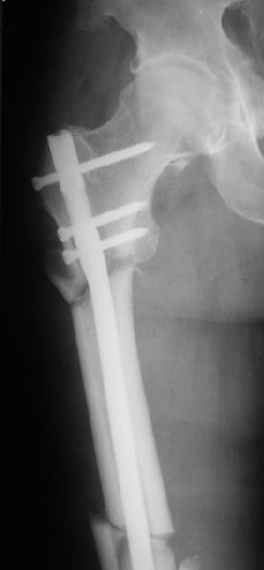

При межвертельных переломах с цефаломедуллярными гвоздями бывает, что проксимальый винт проходит или черед периферический отломок, или прямо над ним. И если остался диастаз, то этот винт при осевой нагрузке не дает сблизиться отломкам. Пример такого остеосинтеза в застарелом случае в приложении.

Могу скромно напомнить о существовании стержня нашей модификации.

В частности, на проксимальном конце сделано еще одно дополнительное статическое отверстие. Можно ввести в проксимальном отделе 4 винта, из них 3 статические (2 в круглые отверстия и 1 по нижнему краю овального). Картинки в приложении. На дистальном конце стержня тоже кое-что улучшено. Спрашивайте в аптеках, как говорится. Выпускается предприятием "ЦИТО" (Москва), то есть это малобюджетное решение.

Конечно, мы не синтезируем остеопорозые вертельные переломы согласно прилагаемому примеру, винты 6 мм вырежутся. Но у более молодых при хорошем качестве кости такие или подобные гвозди с поперечным расположением винтов вполне применимы для меж- и подвертельных переломов.

Картинка красивая, но на мой взгляд, не совсем оптимальная: Слишком медиально введён стержень - риск аваскулярного некроза головки бедра.

вариант межфрагментарного шинирования - зона достаточно простительная т.е. чрезвертельные переломы потенциально хорошо срастаются при любом

расположении сопредельных отломков- хорошая локальная васкуляризация. В приведённом случае я бы предпочёл принцип межфрагментарной компрессии (рекон/гамма нэйл 130- 135) принципу шинирования перелома.

Женя, эта картинка показывает не оптимальное лечение вертельных переломов в моем представлении, а особенности дизайна упомяутого фиксатора.

В частности, его возможности при фиксации переломов проксимального отдела бедра - в сравнении с другими, имеюшими лишь по одному статическому и динамическому отверстию и с кондуктором для введения 2 винтов.

Это было года 2,5 назад, мы тогда еще уточняли возможности шинирования с угловой стабильностью гвоздем с поперечным расположением винтов при переломах проксимального отдела бедра. Пациенту не пришлось приобретать намного более дорогой рекон или проксимальный гвоздь. В приложении еще несколько примеров применения того гвоздя при высоких переломах бедра, в том числе с более латеральной точкой входа. Гвоздь изгибаем для этого.